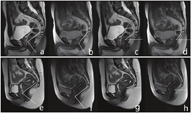

(1) H线(H Line):正中矢状位T2WI图像上耻骨联合下缘到肛管直肠交界处后壁的距离,表示肛提肌裂隙的前后径(图1a~d)。

a、b:男性,28岁,静态H线约48.20 mm,M线约17.41 mm,BN-PCL线约22.88 mm,动态最大力排相H线增加至约54.66 mm,M线增加至约32.22 mm,BN-PCL线减小至约6.66 mm c、d:女性,26岁,静态H线约41.23 mm,M线约13.11 mm,BN-PCL线约19.90 mm,U-PCL线约22.73 mm,动态最大力排相H线增加至约48.49 mm,M线增加至约21.71 mm,BN-PCL线减小至约10.26 mm, U-PCL线减小至PCL线以下约3.10 mm。

a, b Male, 28 years old, static H line was about 48.20mm, M line was about 17.41mm, BN-PCL line was about 22.88 mm, dynamic maximum force phase H line increased to about 54.66mm, M line increased to about 32.22 mm BN-PCL line decreased to about 6.66mm. c, d Female, 26 years old, static H line was about 41.23 mm, M line was about 13.11 mm, BN-PCL line was about 19.90mm, U-PCL line was about 22.73 mm, dynamic maximum force phase H line increased to about 48.49mm, M line increased to about 21.71 mm, BN-PCL line decreased to about 10.26mm, U-PCL line decreased to about 3.1 mm below the PCL line.

(2) M线(M Line):肛管直肠交界处到耻骨尾骨线(pubococcygeal line,PCL)的垂直距离,表示肛提肌裂隙的下降程度(图1a~d)。

(3)膀胱颈(bladder neck,BN)到PCL线的垂直距离(BN-PCL)(图1a~d)。

(4)子宫(uterus,U)到PCL线的垂直距离(U-PCL)(图1c、图1d)。